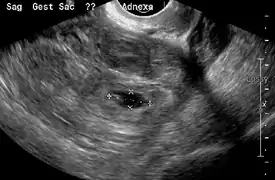

Transvaginal ultrasonography

An ultrasound showing a gestational sac with fetal heart in the fallopian tube has a very high specificity of ectopic pregnancy. It involves a long, thin transducer, covered with the conducting gel and a plastic/latex sheath and inserted into the vagina.[32] Transvaginal ultrasonography has a sensitivity of at least 90% for ectopic pregnancy.[5] The diagnostic ultrasonographic finding in ectopic pregnancy is an adnexal mass that moves separately from the ovary. In around 60% of cases, it is an inhomogeneous or a noncystic adnexal mass sometimes known as the "blob sign". It is generally spherical, but a more tubular appearance may be seen in case of hematosalpinx. This sign has been estimated to have a sensitivity of 84% and specificity of 99% in diagnosing ectopic pregnancy.[5] In the study estimating these values, the blob sign had a positive predictive value of 96% and a negative predictive value of 95%.[5] The visualization of an empty extrauterine gestational sac is sometimes known as the "bagel sign", and is present in around 20% of cases.[5] In another 20% of cases, there is visualization of a gestational sac containing a yolk sac or an embryo.[5] Ectopic pregnancies where there is visualization of cardiac activity are sometimes termed "viable ectopic".[5]

A pregnancy not in the uterus[33]

The combination of a positive pregnancy test and the presence of what appears to be a normal intrauterine pregnancy does not exclude an ectopic pregnancy, since there may be either a heterotopic pregnancy or a "pseudosac", which is a collection of within the endometrial cavity that may be seen in up to 20% of women.[5]

A small amount of anechogenic-free fluid in the recto-uterine pouch is commonly found in both intrauterine and ectopic pregnancies.[5] The presence of echogenic fluid is estimated at between 28 and 56% of women with an ectopic pregnancy, and strongly indicates the presence of hemoperitoneum.[5] However, it does not necessarily result from tubal rupture but is commonly a result from leakage from the distal tubal opening.[5] As a rule of thumb, the finding of free fluid is significant if it reaches the fundus or is present in the vesico-uterine pouch.[5] A further marker of serious intra-abdominal bleeding is the presence of fluid in the hepatorenal recess of the subhepatic space.[5]